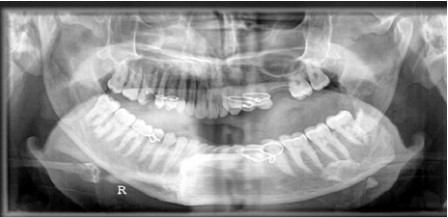

Fig 2: Coronal C.T of displaced angle fracture associated with impacted lower third molar

In this study, 7 cases associated with impacted third molar represented sever displacement of the angle fracture (figure 1, 2) and interfered with achievement of reduction. In four cases, extraction of the impacted lower third molar was done to achieve good reduction at the fracture site. The remaining three cases that were treated without extraction of the lower third molar required more time to obtained good reduction (time range from 30-45 minutes) and exhibited postoperative infection and delayed healing in the fracture site and underwent a second operation for removal of the lower third molar.

In our study, the presence of completely impacted lower third molar provided more risk not only to the fracture but also to degree of the displacement of the fracture site because the tooth occupies more osseous space which could affect the postoperative result. This result agreed with the result of the study that was done by Reitzik et al (22) .